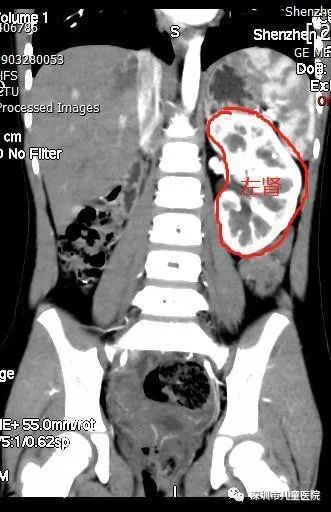

在一次超声检查中,医生告诉他们一个惊人的消息:小美只有一个左肾,却没有右肾。不过,她的左肾没有任何积水,输尿管、膀胱也没有看到任何异常。

他当即给小美开了一个超声检查单。检查发现,小美的膀胱右后方有一个内径2.5mm、长约3cm的管状回声,这高度符合“输尿管异位开口”。

但是,在对小美进一步做核磁共振检查时,轮到医生“吃鲸”了:检查中并没有发现小美的右肾,更不用说与右肾相接的输尿管。

本来快要明朗的事情,又重归混沌。就在这时,事情又有了转机:得知小美的情况后,泌尿外科孙俊杰副主任提出,再做一个CT增强检查。

果不其然,这次,在她的右侧盆腔发现了一个蚕豆大小的、功能很微弱的肾脏。原来,小美的右肾并没有凭空消失,而是“跑”到了盆腔,在这里安了家。

至此,谜团终于被揭开了:

她的右肾发育不良,右肾异位(盆腔),右侧输尿管异位开口。 来,小美的右肾并没有凭空消失,而是“跑”到了盆腔,在这里安了家。